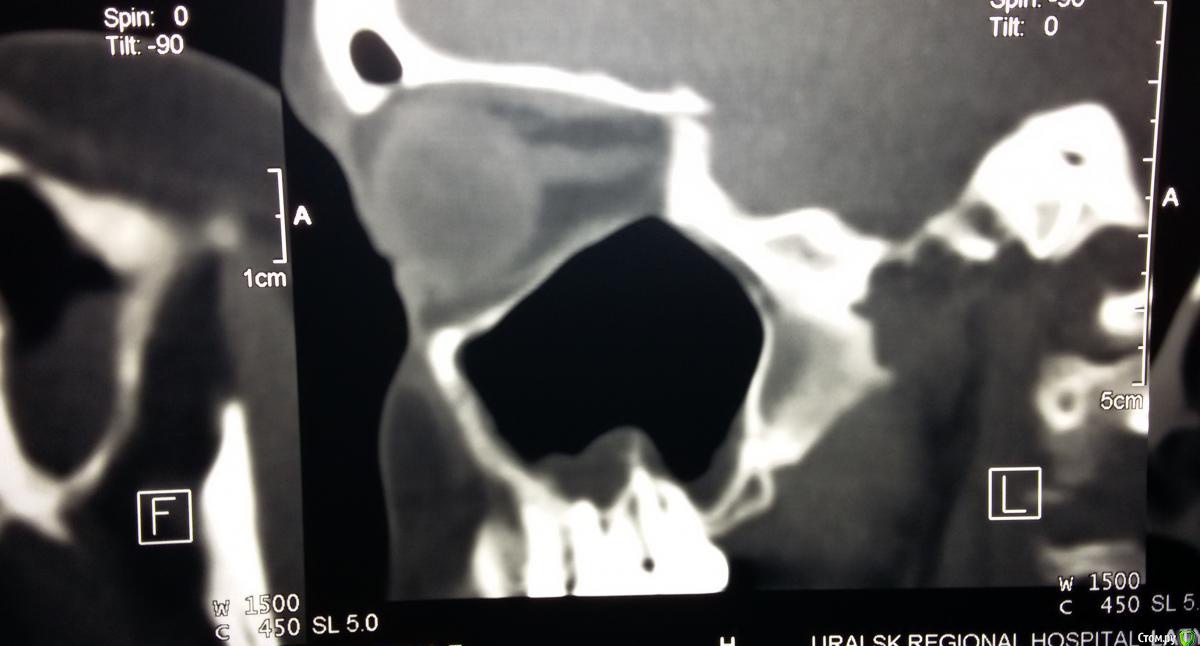

VELICOPTER Опубликовано 15 августа, 2016 Поделиться Опубликовано 15 августа, 2016 Добрый день! Меня мучает постоянная ноющая боль верхнего зуба -пятерки-шестерки, при этом постоянный насморк и немеет вся верхняя челюсть с этой стороны.Сделала КТ на снимке видно,что у последних трех зубов в районе корней идет воспаление.Ходила к стоматологу - он сказал ,что идет воспаление в районе 5-6 зуба ,пролечили их по очереди.Когда мне зуб вскрывают - промывают и ставят временную пломбу боли пропадают , но как-только установят постоянную пломбу ,примерно через месяц опять начинается отек и насморк с правой стороны и немеет верхняя часть.Последний раз шестерку запломбировали 28/06/2016г, но с 10/08 боли возвратились ,реагирует на горячее и боль при жевании,и также появился насморк только с этой стороны.Прилагаю КТ до лечения , но сейчас симптомы те же самые что и после лечения.Подскажите что это может быть ? Ссылка на комментарий

DmitrySH Опубликовано 15 августа, 2016 Поделиться Опубликовано 15 августа, 2016 Выложенный фрагмент КТ совсем не информативен 1 Ссылка на комментарий